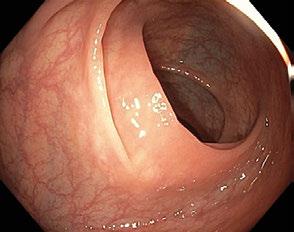

Obr. 1.2 Anální kanál v prográdním pohledu s patrným přechodem kolumnární a skvamózní sliznice (linea dentata)